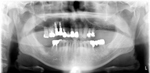

レントゲン写真

治療前 レントゲン写真

治療後 レントゲン写真

60才代 男性

総額:530万円(税別)

治療期間:2年

リスク副作用:経年的変化による補綴物の消耗。ブラッシング不足ですとインプラント周囲炎になります。